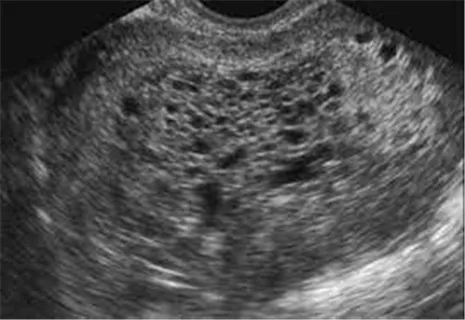

산과력 0-0-1-0인 31세 여성이 불규칙한 질출혈과 하복부 통증을 호소하며 병원을 방문했다. 환자는 평소 25~35일 간격의 월경주기를 가지고 있으며, 마지막 월경 후 10주가 지났다고 한다. 골반 검진 결과, 자궁은 임신 12주 크기로 촉진되었고, 왼쪽 난소는 성인 주먹만하며, 오른쪽 난소는 그보다 작게 느껴졌다. 검사 결과 및 초음파 소견은 아래와 같다. 이 환자에게 적절한 처치는 무엇인가?

LMP 10주의 여성에서 임신 12주 크기로 증가되어 있는 자궁, 왼쪽 난소가 주먹 크기로 촉진되고 있다. 초음파에서는 "snowstrom appearance"가 나타나고 있고, b-hCG가 매우 증가되어 있어 포상기태를 의심할 수 있다. 폐경기 여성에서는 자궁절제술을 시행할 수도 있으나, 분만력이 없는 젊은 여성이기 때문에 fertility를 생각해서 자궁내막긁음술(D&C)을 시행한다. 자궁내막긁어냄술은 진단과 치료를 동시에 시행할 수 있다.